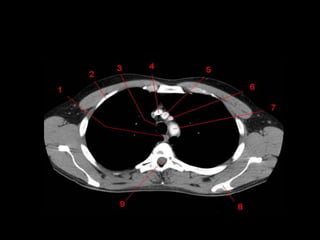

Mediastino Médio

• Pericárdio e seu conteúdo, arco aórtico e as

grandes artérias proximais, as artérias e veias

pulmonares centrais, traquéia, brônquios

principais e linfonodos.

• Nervo frênico e vago não são visíveis a TC.

• Janela Aortopulmonar

– Tecido adiposo, linfonodos, ligamento arterial e

nervo laringeo recorrente.

Tronco Pulmonar e Janela Aortopulmonar

• Inferior ao

arco aórtico e

a Esquerda

da traquéia

• Medial:

Traquéia, BPE

esofago.

• Lateral:

Superficie

Pleural do

lobo superior

esquerdo.